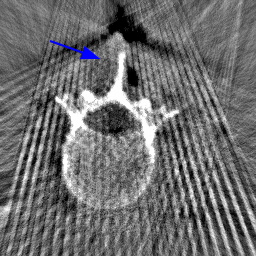

Disentanglement and explicit shape constraints. As shown in Fig. 4, we can see streak metal artifacts nearly everywhere in . M1 can roughly disentangle artifacts and anatomical information but strong vertical artifacts and strange air area appear in (see red arrows of M1 in Fig. 4). For the anatomical structure, M1 learns to segment vertebrae with fully supervised and applied on various CT images, but fails to suppress the false bony structure in and as may misclassify some metal artifacts as bone.

Implicit shape constraints. With , all segmentations are improved with higher Dices and smaller ASDs, see Table 1. As shown in Fig. 4, , and become similar but the high density bone is not correctly segmented in as it maybe treated as metal artifacts. Comparing between M2 and M1, the abnormal air region disappears but metal artifact reduction performance is still not satisfactory.

Anatomy-aware generation. With AADE layer in M3, , and are substantially improved as shown in Table 1. Note, is used as attention map, so we do not expect it to be identical to . In , metal artifacts are further suppressed comparing with M2. Thus, AADE is critical to our anatomy-aware artifact disentanglement framework. With the special structure, can be punished in the image translation and reconstruction processes and the other encoders and generators receive more guidance. However, as shown by blue arrows in Fig. 4, we observe a shadow of vertebra edge of appears in of M3 and the vertebra boundaries get smoothed out in . It may be because sharp edges are encoded as metal artifacts and forced to be added to by artifact consistency loss .

Removal of . To mitigate vertebrae shadows, we remove . The segmentation performance of most images in M4 gets improved because of better synthetic images. Overall, in M4 yields the best segmentation performance for CBCT images with an average Dice of 0.847 and an average ASD of 1.54 mm. For the synthetic images, M4 generates with the best quality and least metal artifacts among all the models. M4 also outputs without vertebra shadows. The results indicate our shape-aware network could preserve anatomical details and transfer the metal artifacts precisely without .